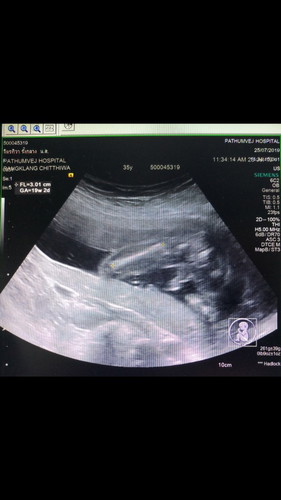

แบบนี้เป็นผู้ชายหรือเปล่าค่ะ คือคุณพ่อเขาบอกไม่มั่นใจค่ะ แต่หมอก็บอกว่าชัวผู้ชาย 100% มีใครอัลตร้าซาวเจอแบบนี้แล้วไม่ใช่ผู้ชายไหมค่ะ